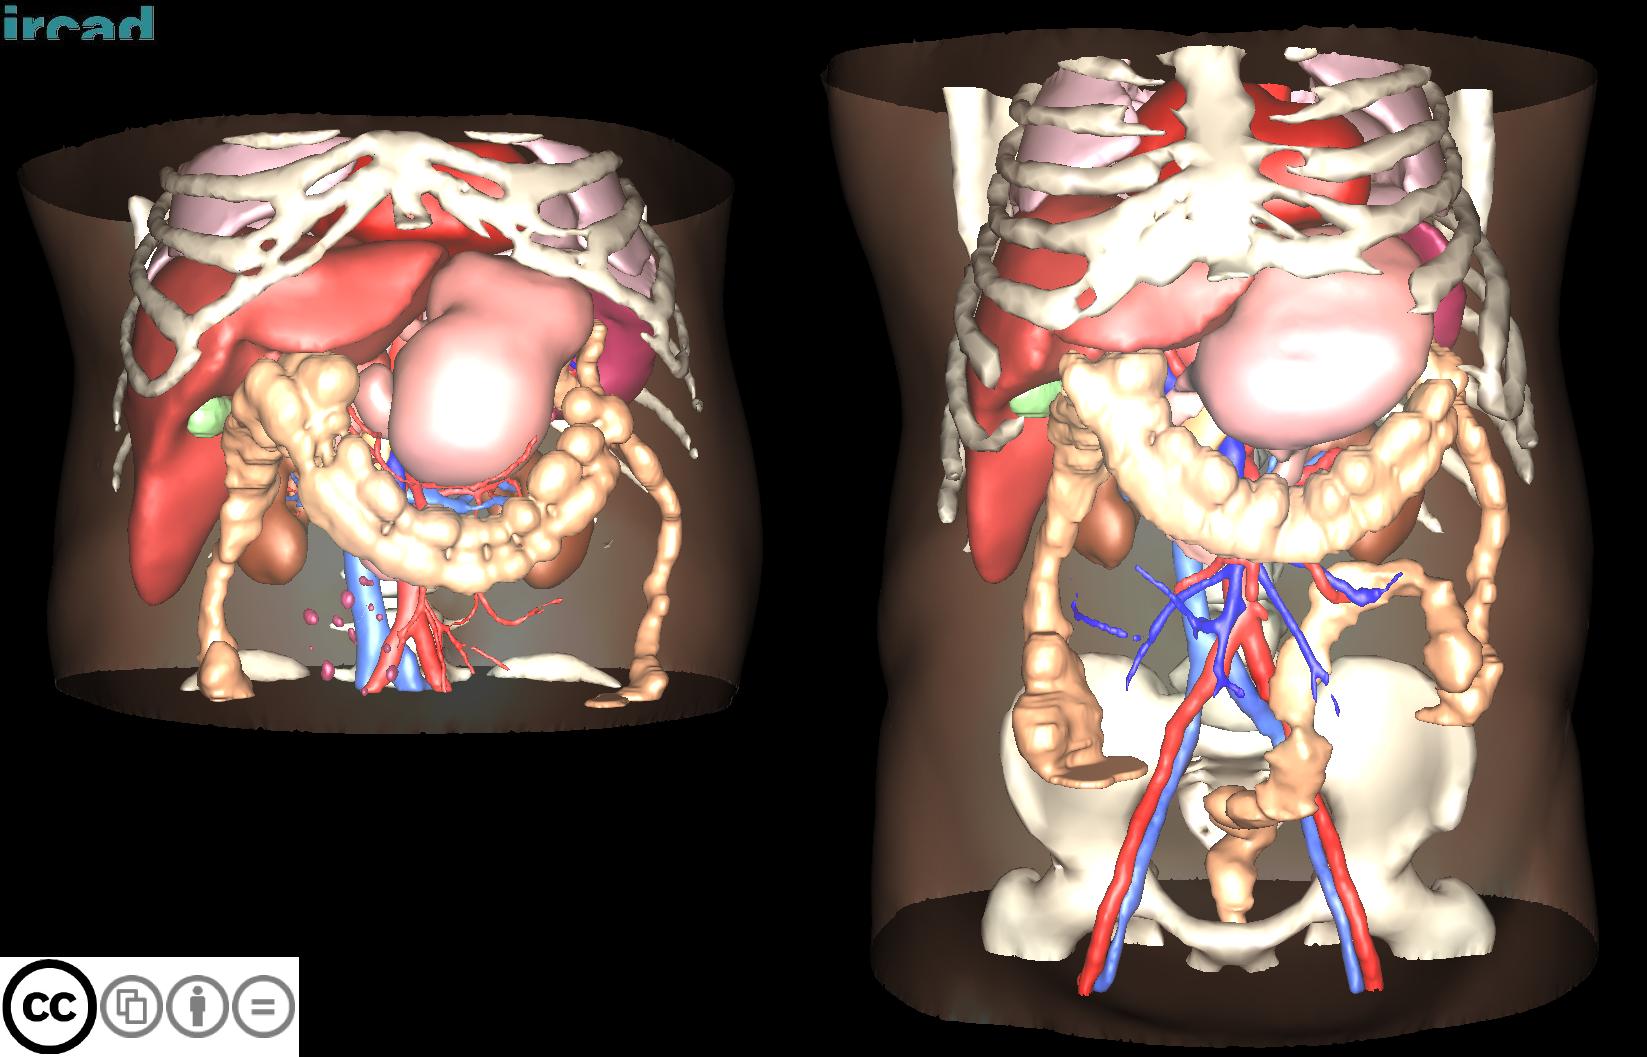

3D-IRCADB

| 3D-IRCADb 01 02 | 肝脏/肝肿瘤 | 分割 | CT | 20+2 | surface mesh | dcm | CC |

3D-IRCADb是比较早的一个数据集,有两个子集,分别包含20组和2组CT片子。